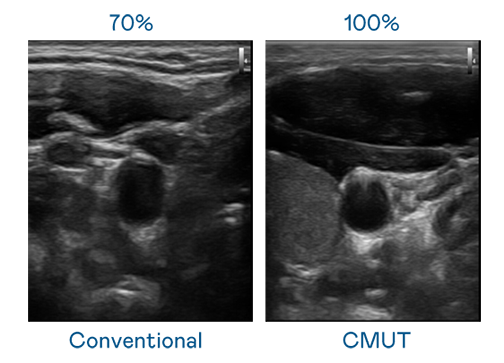

CMUT 技术是一种用电容式微机电元件来产生超音波讯号的技术。与传统 PZT 压电式技术相比,CMUT 频宽增加 30%,更宽频的超音波讯号让影像解析度大幅提升,是实现高影像品质医疗超音波扫描、促进精准医疗发展的关键技术。

超音波影像的解析度高低,首先取决于探头能发出的讯号频宽。东升国际 CMUT 可提供高清晰的超音波讯号,提供高频宽、高灵敏度、影像纹理细节更高的超音波影像,协助医护人员缩短影像判读时间及利用精准的医疗影像进行诊断。